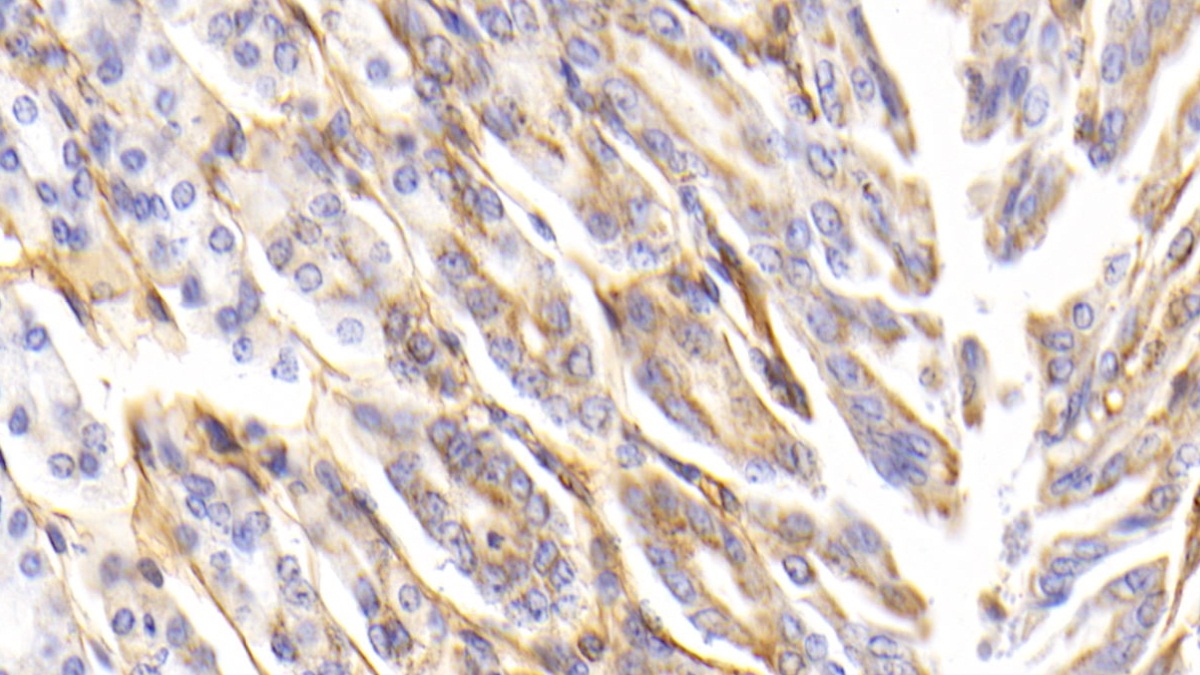

Использование высококачественных первичных антител является неотъемлемым условием получения точных и воспроизводимых результатов в современных научных исследованиях. Например, в рамках онкологического исследования удалось достоверно идентифицировать экспрессию белка PD-L1, что сыграло ключевую роль в оценке потенциальной эффективности иммунотерапии. Применение надежных антител обеспечило стабильность сигнала и высокую специфичность детекции, что позволило получить данные, пригодные для публикации в рецензируемых научных изданиях.